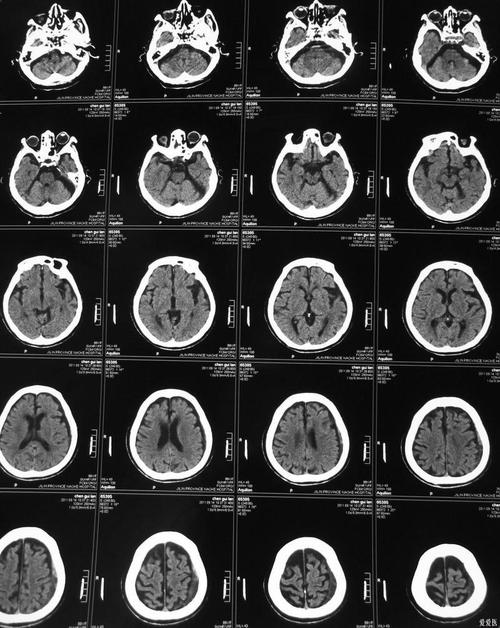

(图片来源网络,侵删)- 普通平扫CT:它主要是看密度变化,在发病超早期(6小时内),可能看不到明显异常,几小时到几天后,坏死的脑细胞会因为水肿而密度变低,这时才能看到低密度的梗死灶,但它无法区分哪些是已经坏死的“核心区”,哪些是濒临死亡的“半暗带”,它只能看到一个“模糊”的梗死整体。